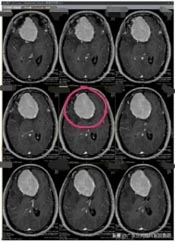

近段时间来,林阿姨头痛越来越重,偶尔还会出现小便失禁,林阿姨这才有所警觉。在医院头颅CT检查,显示:前颅底巨大占位,考虑脑膜瘤可能性大。林阿姨吓坏了,半辈子都平平安安,想不到脑子里居然有这么大的一个肿瘤。

孩子们也非常担忧,通过四处打听,林阿姨来到了广东三九脑科医院。进一步影像检查也提示是:前颅窝底巨大占位性病变,考虑脑膜瘤可能性大。

肿瘤体积巨大,占位明显,医院副院长、神经外五科主任鲁明和团队一起经过讨论,快速制定了安全且风险较小的手术方案,术中需要避开重要血管,尽最大可能全切除肿瘤。术前进行全脑血管造影,影像显示:前颅底异常染色,呈类圆形,肿瘤主要是由右侧脑膜中动脉前支、右侧眼动脉分支参与供血;决定先行肿瘤栓塞术,术后加压包扎送病人至手术室,行“前颅底巨大脑膜瘤切除术”。肿瘤周围血管丰富,已侵犯重要神经;导航准确定位,显微镜下见肿瘤起源于大脑镰及前颅底,阻断肿瘤血供后,先钨刀切除左侧额部部分肿瘤,再超吸切进行瘤内减压,最终镜下将肿瘤切除干净。